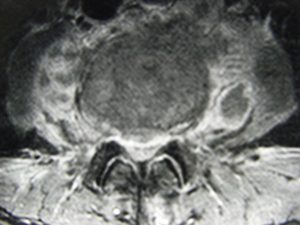

Εικόνα 3 (α,β,γ,δ,ε,ζ)

Μαγνητική Τομογραφία της Ο.Μ.Σ.Σ. (13/06/2007) Ακολουθία Τ1 και Τ2

Οβελιαία τομή (α,β) Παρατηρείται η ύπαρξη Επισκληριδίου Αποστήματος στο επίπεδο Ο3-Ο4 που προκαλεί μεγάλη στένωση του σπονδυλικού σωλήνα, με απώθηση του νωτιαίου σάκου. Διαπιστώνεται επίσης η ύπαρξη παρα-σπονδυλικού αποστήματος

Εγκαρσία τομή (γ,δ) Παρατηρείται η ύπαρξη Επισκληριδίου όπως επίσης και προ-παρασπονδυλικού αποστήματος.